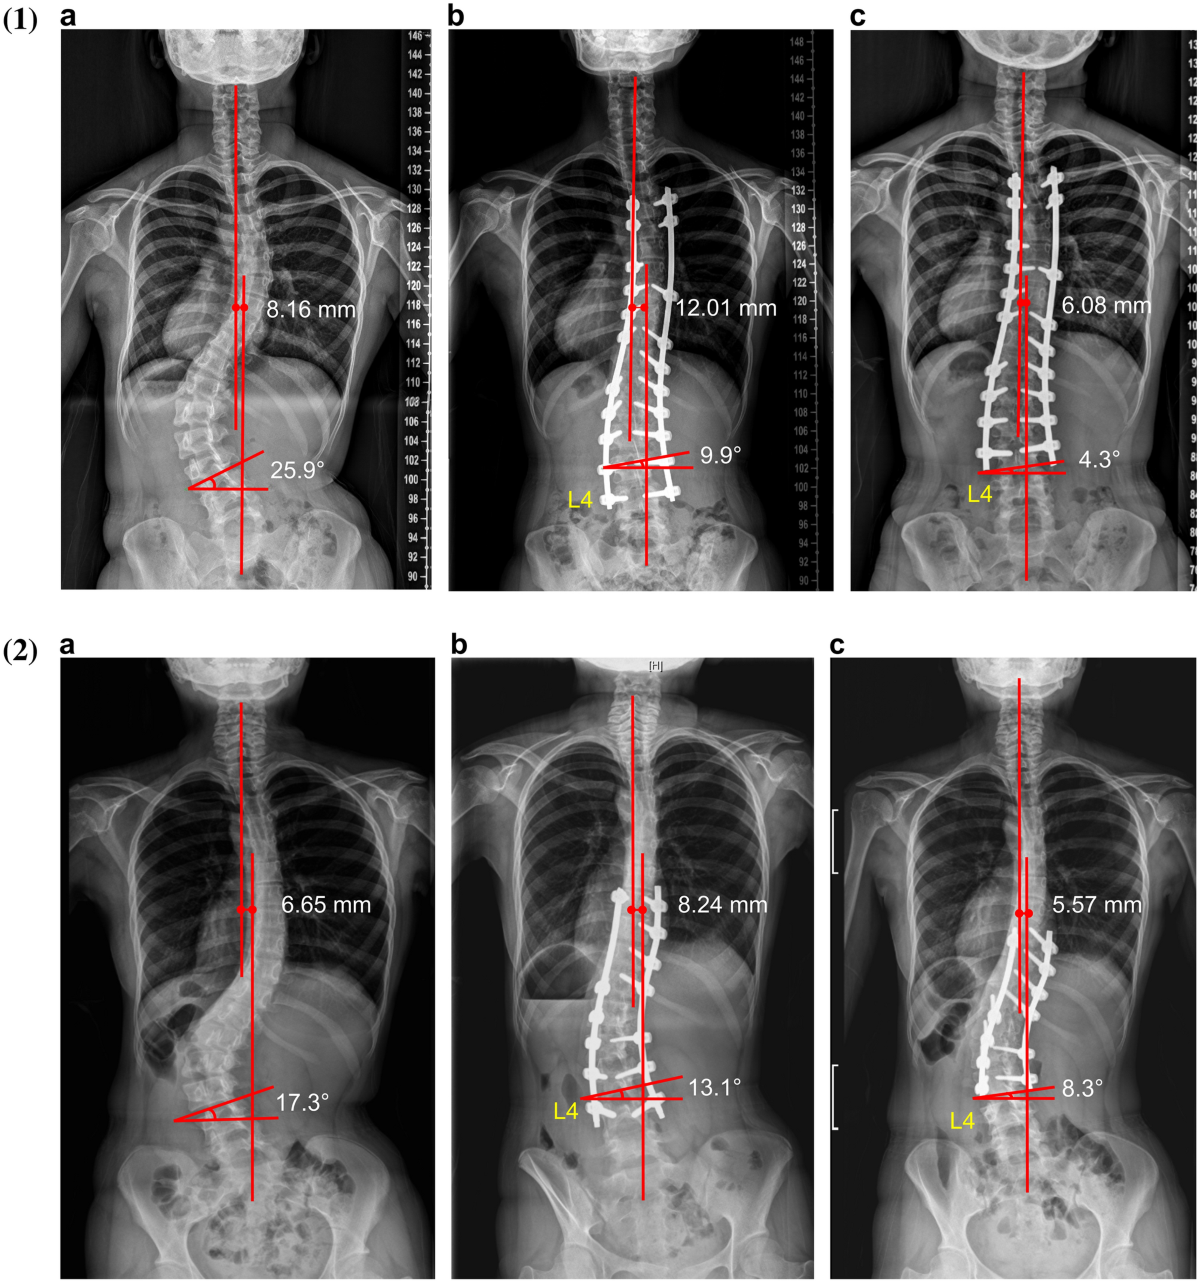

قامت إحدى الدراسات الحديثة بتحليل ثلاث تقنيات رئيسية مستخدمة في جراحة اعوجاج العمود الفقري. وتمت مقارنة كل منها من حيث الضغط، والشدّ، والإجهاد الواقع على الأعصاب والحبل الشوكي.

1. تقنية هارينغتون (Harrington Distraction)

وهي أقدم تقنية، وتعتمد على السحب الطولي للعمود الفقري.

تأثيراتها على الأعصاب:

تولّد أعلى إجهاد على الحبل الشوكي

تسبب ضغطًا كبيرًا خصوصًا في المنطقة الصدرية القطنية

تزيد الشدّ على الأعصاب بنسبة أكبر من التقنيات الحديثة

النتيجة:

هذه التقنية فعّالة لكنها الأكثر إجهادًا للأعصاب مقارنة بباقي الطرق.

2. تقنية الأزاحة (Segmental Translation)

تعتمد هذه التقنية على دفع الفقرات جانبياً لتعود إلى خطها الطبيعي.

التأثيرات العصبية حسب الدراسة:

زيادة في إجهاد القص (Shear Stress) بنسبة 15%

زيادة في الاستطالة العصبية بنسبة 25%

انخفاض في ضغط الأعصاب بنسبة 62% مقارنة بتقنية هارينغتون

رغم أنّها تضيف بعض الإجهاد، إلا أنها أكثر لطفًا على الأعصاب من تقنية هارينغتون.

3. تقنية الدوران (Segmental Derotation)

وهي من أكثر التقنيات استخدامًا اليوم، وتعتمد على تدوير الفقرات لإعادتها لوضعها الصحيح.

التأثيرات العصبية:

انخفاض إجهاد القص بنسبة 25%

زيادة طفيفة في الاستطالة بنسبة 18%

انخفاض في الضغط على الحبل الشوكي بنسبة 72%

انخفاض ضغط الأعصاب بنسبة 57%

تحسن واضح في الضغط الداخلي للحبل الشوكي بنسبة 7%

هذه التقنية الأكثر أمانًا عصبيًا بحسب الدراسة، خاصة في المنطقة الصدرية العليا.